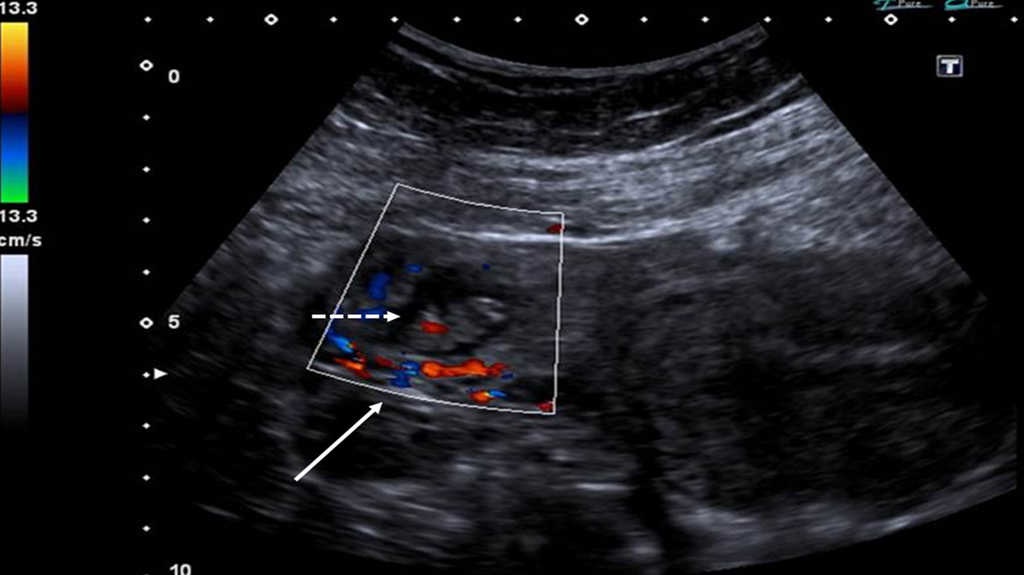

El signo del anillo tubario plantea como principales diagn??sticos diferenciales otras masas anexiales, como el cuerpo l??teo, el hematosalpinx y el hematoma p??lvico.

Es posible diferenciar el anillo tubario del hematosalpinx y del hematoma p??lvico debido a que los dos ??ltimos carecen de flujo ante la evaluaci??n mediante ecograf??a Doppler color.

Tanto el anillo tubario como el cuerpo l??teo presentan una corona hipervascular en la evaluaci??n Doppler color que se comporta como un hallazgo poco espec??fico, pero muy sensible2,5 (fig. 4).